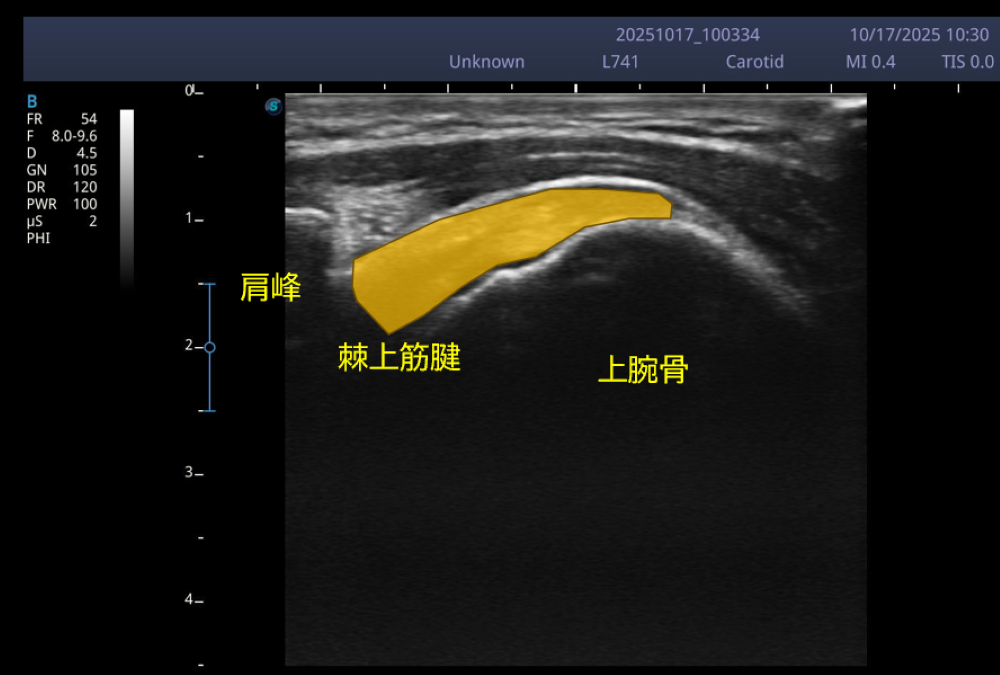

[エコー問題の解答例]

※画像は筆者が作成